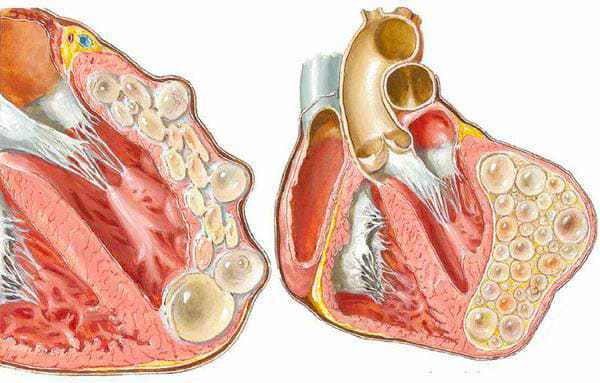

Поряд із ними існують тисячі паразитів, які можуть жити у вашій печінці, мозку, легенях, крові, шлунку. І практично всі вони є смертельними. Частина відразу починає діяти агресивно і руйнує організм. Частина – до певного часу діє непомітно, поки їх кількість не стане такою, що організм-носій вже не може витримувати і людина вмирає. Вони провокують масу смертельних ускладнень: інфаркти, ракові пухлини, цироз печінки, нефрит, розкладання нирок та сотні інших, більш рідкісних, але не менш смертельних.

3. Ехінококові кісти серця. Зараження пацієнта ехінококами було виявлено надто пізно. Лікуючий лікар вважав, що в нього просто ішемічна хвороба серця і стенокардія, але правда виявилася значно більшою. жорстокий. Оперувати було вже марно, а консерватине лікування не дало плодів. Замінити серце теж не вийшло - не було донорів. У результаті пацієнт помер не приходячи до тями.